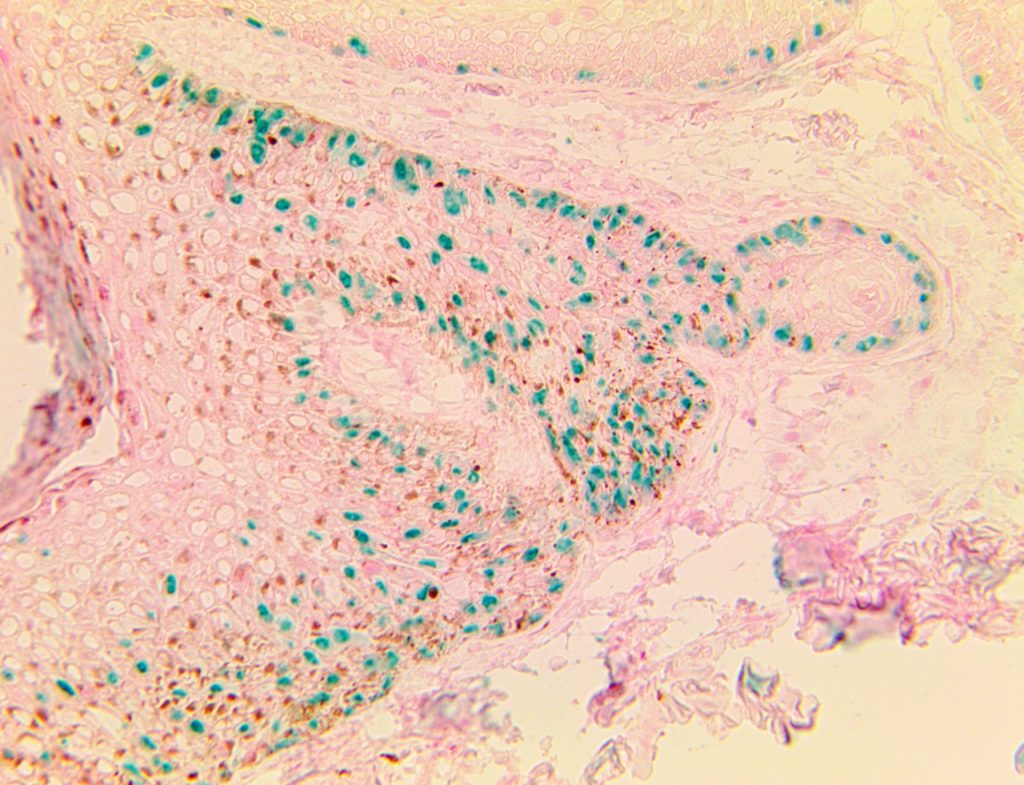

Bio SB has developed high affinity IVD monoclonal antibodies for fast immunohistochemistry (IHC) detection of melanoma, basal cell carcinoma (BCC), squamous cell carcinoma (SCC) and other Mohs surgery related conditions. Combined with our innovative IHC detection systems, we are opening the doors to a faster and more accurate immunohistochemistry applicable to Mohs surgery.

Bio SB has developed a fast, non-biotin monovalent Fab micropolymer IHC detection system for the detection of IVD antibodies for melanoma, BCC, SCC and other Mohs surgery related conditions. Our innovative IHC detection systems have opened the doors for a faster and accurate immunohistochemistry applicable to Mohs surgery.